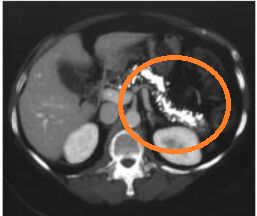

蠻明顯的胰臟形狀的鈣化點

酗酒抽菸超過10年→急性胰臟炎的危險因子

斷斷續續嚴重腹痛→暗示急性胰臟炎反覆發作

沒事多個目前,又沒有體重減輕,只好選(A)不選(B)